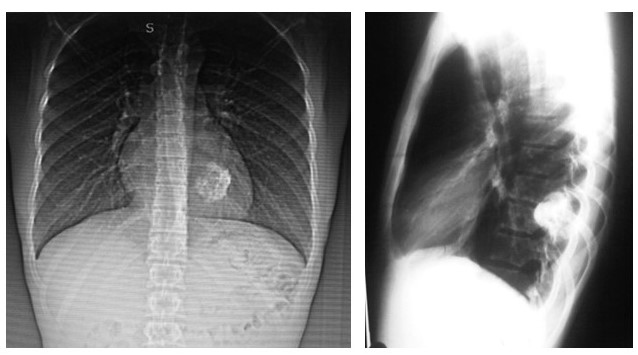

Paciente masculino de 30 años, quien consulta por presentar dolor en región dorsal izquierda, de tres meses de evolución, sin ningún otro acompañante. Al examen físico se constató dolor a la palpación en hemitórax izquierdo sobre el sexto (6o) arco costal posterior, sin alteraciones en la auscultación en ambos campos pulmonares. Se realizaron estudios de laboratorios que estuvieron dentro de los parámetros normales. Los estudios por imágenes como radiografía de tórax y TC evidenciaron; una imagen de defecto, localizada en el ángulo externo del sexto (6o) arco costal, en “pastilla de aspirina”, muy borrosa, de aspecto lítico con aparente abombamiento del periostio y pérdida de sustancia ósea, por lo que se recomienda realizar TC de tórax con ventana ósea y reconstrucción de pared torácica (Figura 1).

La tomografía multidectector, VCT64 de tórax con reconstrucción 3D, en donde se evidenció lesión única, ocupante de espacio la cual afectaba al sexto (6o) arco costal posterior izquierdo. Expansiva, con una porción central hipodensa de comportamiento osteolítico, con remodelación, adelgazamiento y expansión de la cortical, La lesión midió 16 mm x 36,4 mm x 17,5 mm, sin lesiones en los demás planos óseos. No se evidenciaron lesiones focales ni a nivel de la pleura o del parénquima pulmonar (Figura 2).